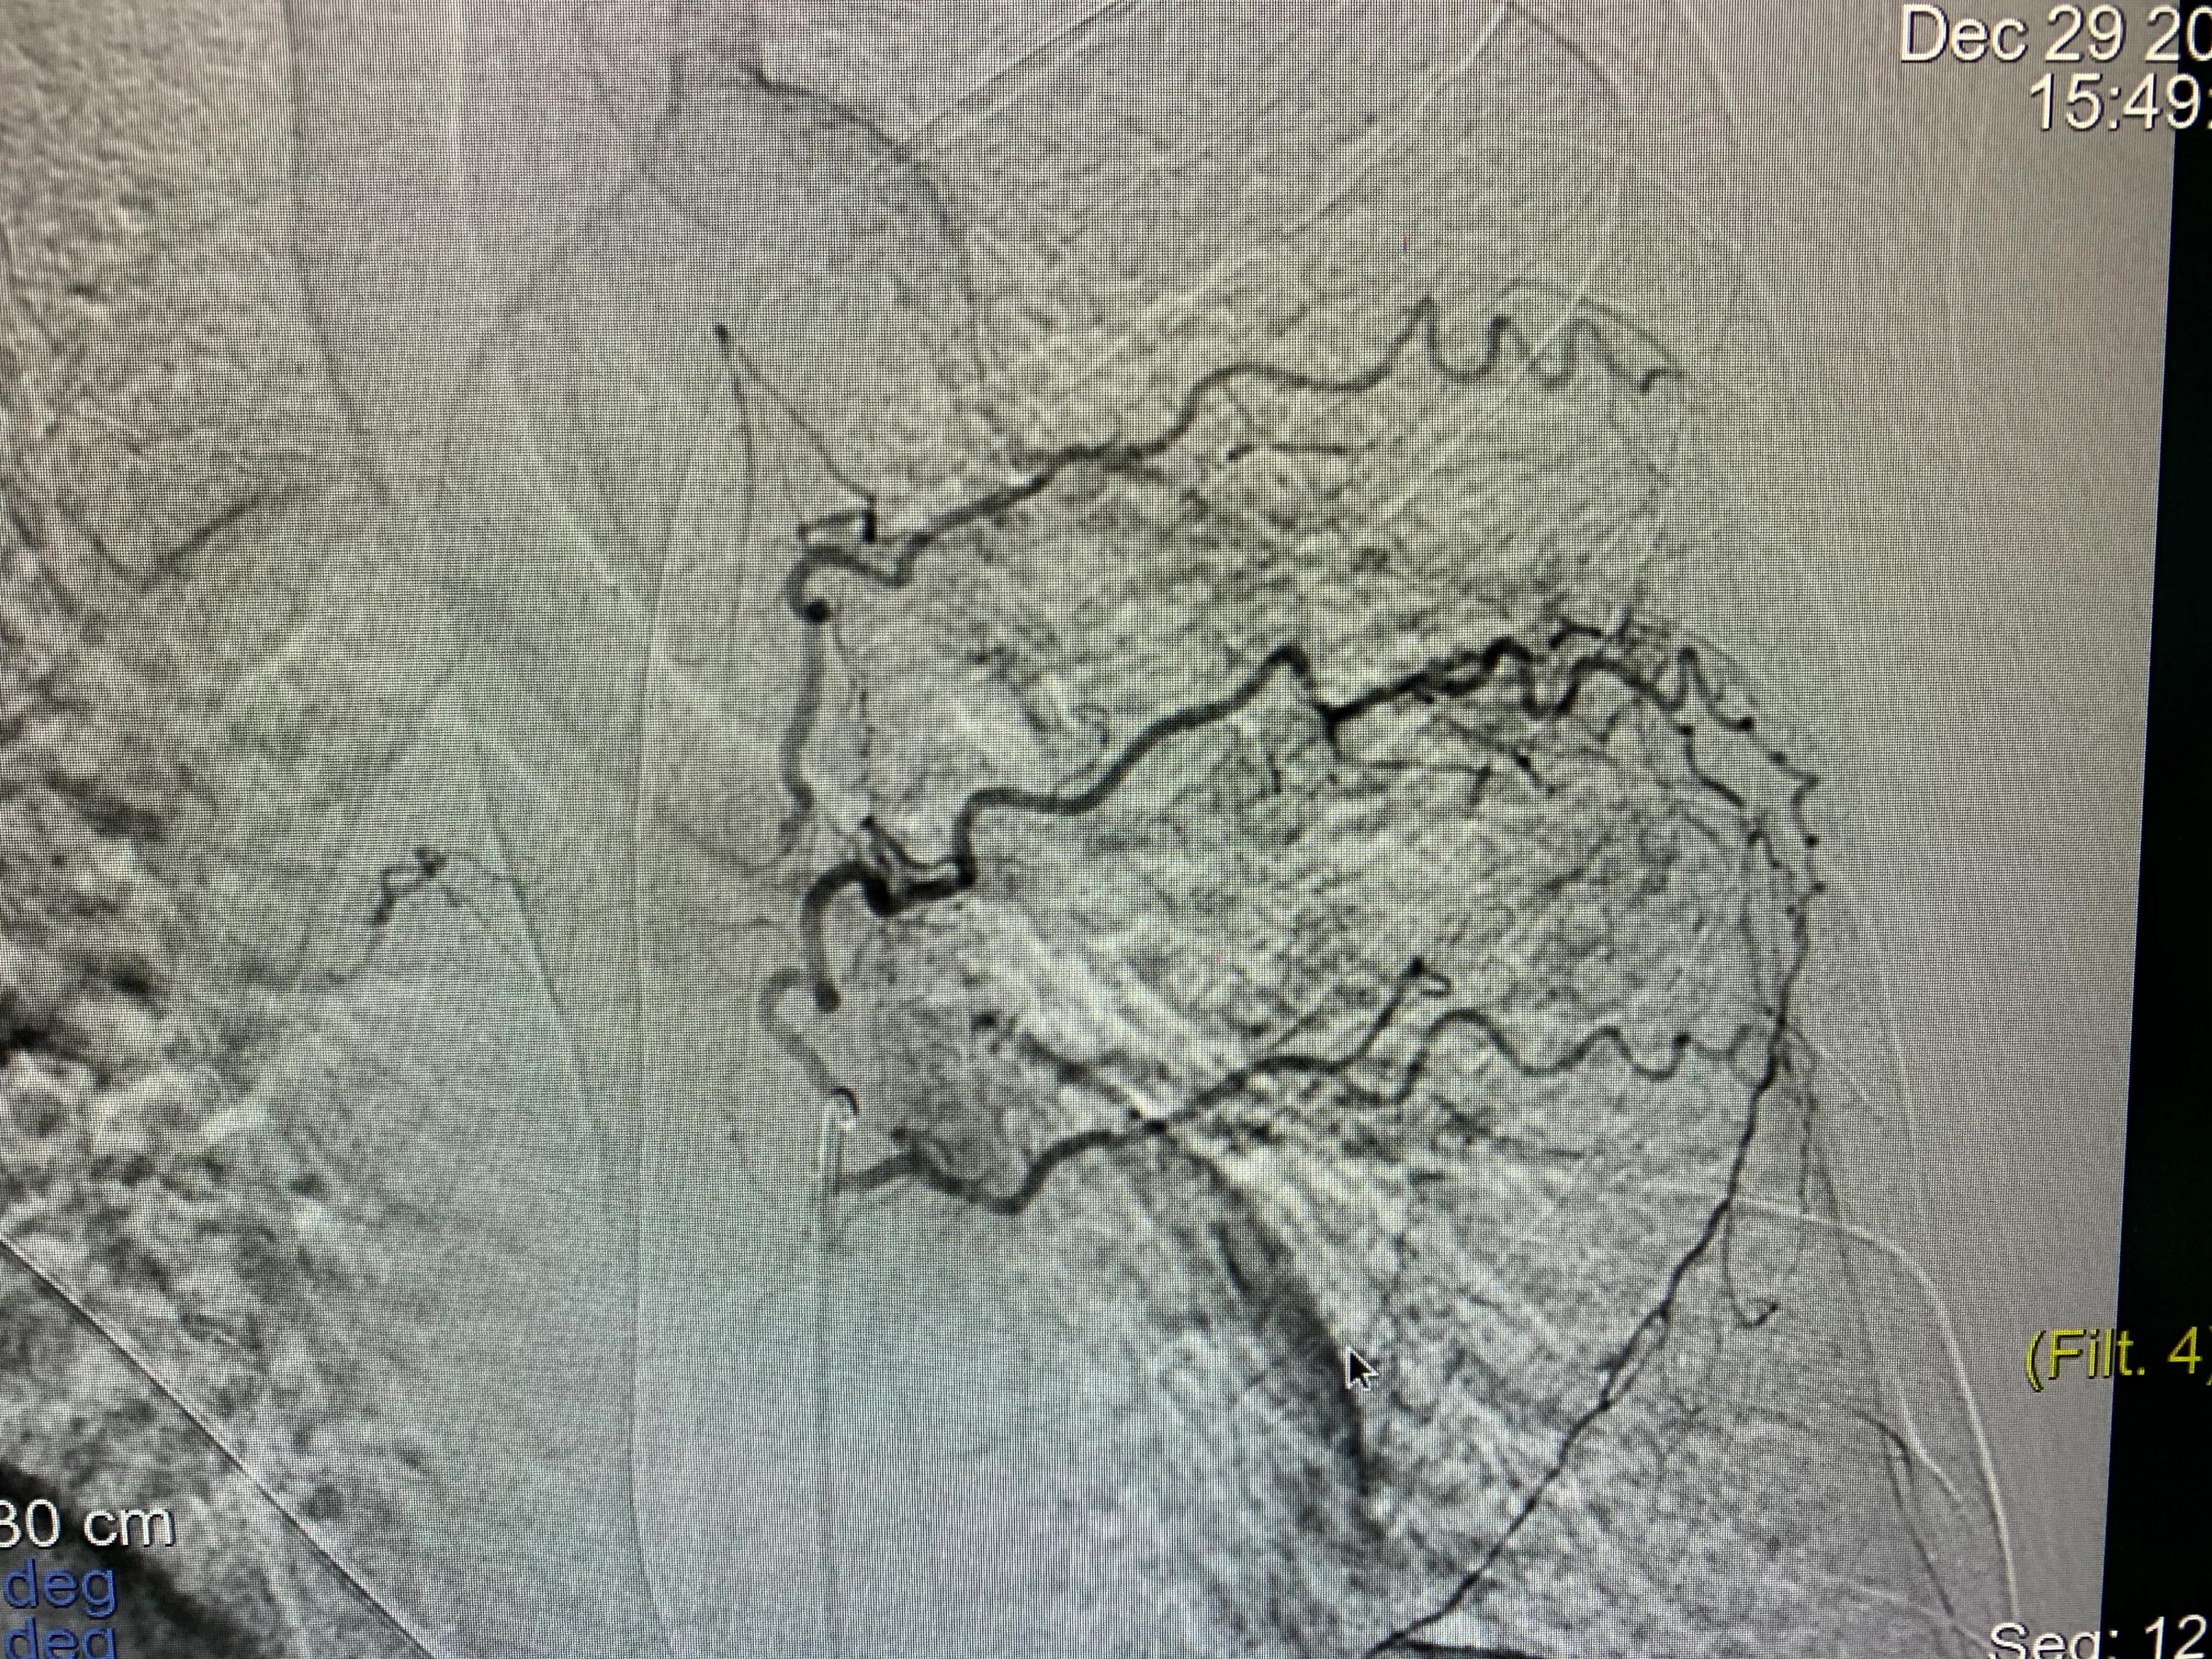

老年男性患者,左肺腺癌,化疗期间出现了咯血,术中可见左侧支气管动脉、左侧多支肋间动脉及左侧胸阔内动脉均参与肿瘤的血供,并可见以上动脉-肺动脉瘘,经肿瘤供血动脉灌注化疗药并且进行栓塞,术后未再出现咯血,一个月复查ct提示肿瘤较前明显减小,阻塞症状较前缓解。微创介入即经导管灌注化疗栓塞治疗肺肿瘤能够有效治疗肿瘤并且缓解肿瘤引起的一系列并发症,如咯血、阻塞性肺炎等,当然,肿瘤的治疗是综合治疗,需要多学科的共同参与。